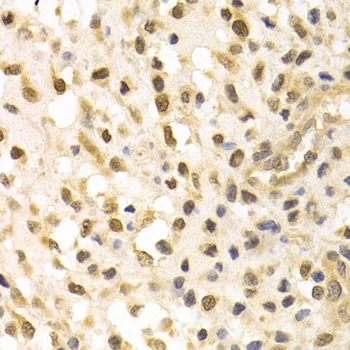

Immunohistochemistry of paraffin-embedded human metrocarcinoma using CUL4A antibody at dilution of 1:200 (400x lens).

Immunohistochemistry of paraffin-embedded human stomach cancer using CUL4A antibody at dilution of 1:200 (400x lens).